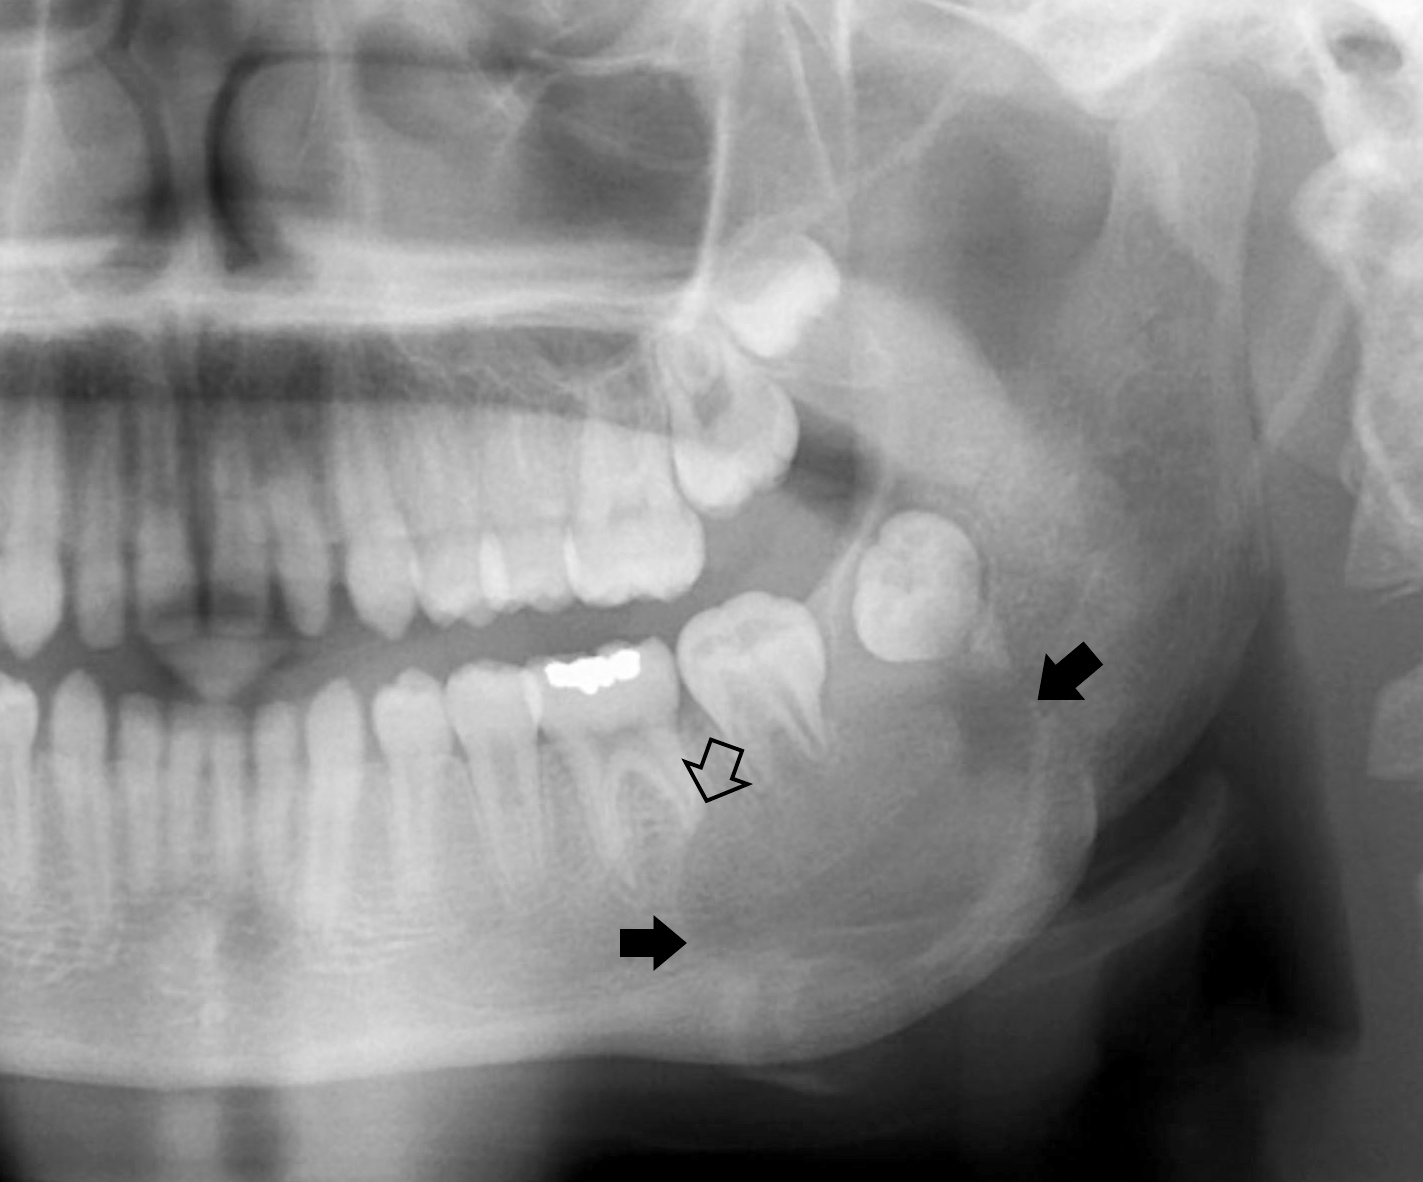

單一囊腫型(unicystic) 下顎後 ~23y

• 預後較多囊好

• 常圍繞未萌發的牙齒,特別是第三大臼齒